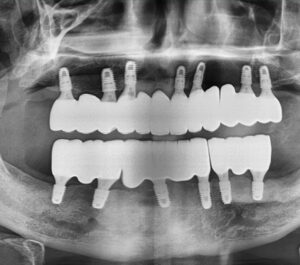

아래 술 후 사진을 보게 되면 상악 7개,

하악 6개의 임플란트를 식립하여

브릿지 형식으로 제작해 상악 12개,

하악 12개의 치아 기능을 회복하였습니다.

임플란트도 일반 보철물과 마찬가지로

브릿지 제작이 가능한데요.